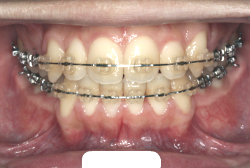

開咬

開咬という症状は、一部の歯が上下的に接触できない症状を持っています。一番よく見られるのは、奥歯は咬めるけれども前歯の部分が咬めない(閉じても前歯同士が当たらないという状態)という症状で、この状態を、前歯部開咬といいます。そのほかに、臼歯部開咬や側方開咬などいろいろ珍しい症状はありますが、通常”開咬”というと”前歯部開咬”のことをいいます。

「前歯が重ならない」という主訴で来院したケースです。診断の結果、「重症の開咬」と判明しました。

この方の場合は、マルチブラケット装置は、歯の位置づけを3次元的に正確に行うことの出来る最善の矯正方法です。したがって開咬の治療も、形の改善としては問題なく行うことが出来ます。しかし、開咬が他の症状と少し違う点は、舌や唇の動かし方に問題があることから生じた症状なので、この問題を放置したまま形だけを作っても、時間が経つと簡単に後戻りしてしまうという問題です。つまり、マルチブラケット法で形態の矯正をするのと同時に、原因となっている筋肉の動きを正常に修正しなければなりません。この筋肉の動きを正常に修正する治療が、"筋機能訓練療法(Myo-functional therapy:略してMFT)"といわれるものです。

筋機能訓練療法は、筋機能訓練療法士という特別なトレーニングを積んだ歯科衛生士が行います。内容的には、いろいろなメニューがあり、簡単なものから始めて少しずつ筋肉の力を強めていき最終的には、無意識に起きる舌の突出をなくし、正しい摂食嚥下運動を獲得するまでトレーニングしていきます。この症例は、もちろん筋機能訓練にもしっかり取り組みました。治療後は開咬が改善しただけでなく、出っ歯の症状もなくなり唇の審美性が大幅に改善しました。もちろん奥歯の噛み合わせも正しい状態が確立しています。